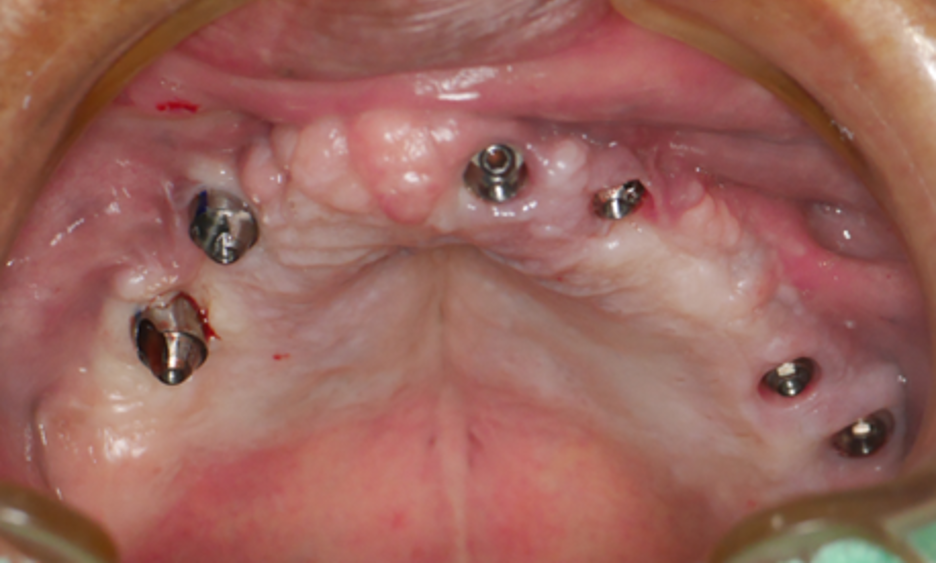

為了徹底解決問題,讓廖阿姨重拾咀嚼能力和生活品質,我們為她規劃了完善的治療方案:植入6顆人工植體作為堅固的「地基」,再裝上全新的固定式假牙(全口固定假牙重建)。

經過詳細的口腔檢查與3D影像分析(如電腦斷層掃描),發現林先生口內狀況如下:

1. 上顎左側十五年前植入的兩顆植體狀況良好,穩固且骨整合佳。

2. 其餘牙齒已缺失,齒槽骨條件在特定區域仍適合植牙。